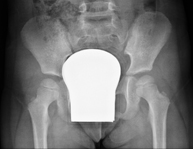

Procediment que permet, mitjançant l'ús de raigs X, i després d'injectar un contrast a l'interior de l'articulació, detectar lesions d'aquestes articulacions (cartílag, os, tendons, etc. ) segons la distribució del contrast. - RX Pelvis

Procediment que usa els raigs X a través de la qual s'obtenen imatges de la pelvis per al seu estudi, especialment dels ossos pèlvics. - RX Edat òssia

Estudi que mitjançant una radiografia de la mà permet valorar, en funció del desenvolupament dels ossos, l'edat del pacient i determinar si existeix un retard o un creixement superior pel que correspon a la seva edat. - RX Malucs pediatria

Estudi que usa els raigs X a través de la qual s'obtenen imatges del maluc i permet descartar luxacions. - RX Seriada òssia